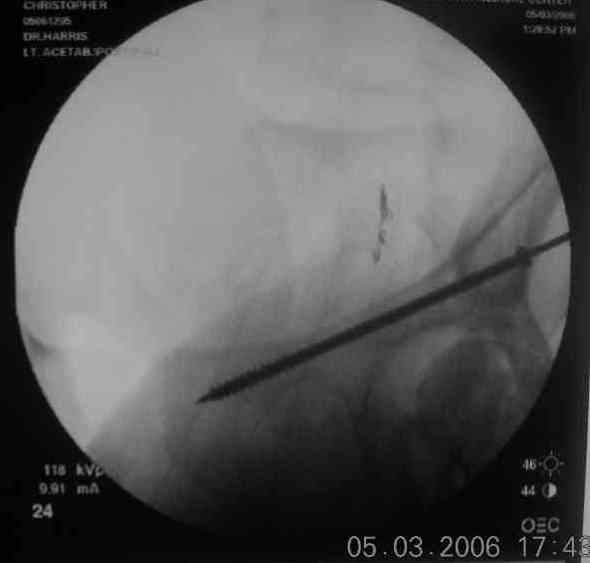

the case that I found is a 20yo male, MCC. his AP pelvis shows an interesting position of his bladder. it is pushed aside by a hematoma from SGA injury. we did a limited lateral window approach for the anterior column first, pt bumped up/supine. then closed and repositioned for KL. I could not find intra-op photos of cases when we did only a small incision for the AC screw (but they do exist!!). the lateral window is available for reduction assessment if a KL approach is being used. in the lateral position this window is available. the prone position definitely takes pressure off of the post column and facilitates reduction. in the lateral position a schantz pin in the ischial tub +/- bone hook in sciatic notch helps with PC reduction. the lateral position also gives better airway access for anesthesia. airway problems are rare, but prone position seems to be a bit more of a challenge to exchange the tube, or reintubate altogether. just something further to debate!

Your lateral intraop image actually made me nauseated... truly a visceral response when I saw it... it's an image which brings back the horrid memories of my past... struggling to achieve my daily malreduction... flipping and flopping the poor patient... reprepping... wasting time... praying... trying to get a C-arm in place... gag... until some kind soul taught me a prone KL.... ahhh, what a great day that was.